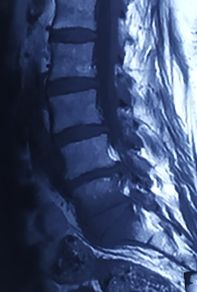

Infective Spondylodiscitis at L5-S1

Imaging studies, including MRI and plain X-rays, confirmed the presence of spondylodiscitis at the L5-S1 level, characterized by destruction of the vertebral end plates and narrowing of the intervertebral disc space. There were also early signs of instability at the lumbosacral junction. The progressive bony destruction was concerning, as it posed risks of persistent pain, deformity, and potential neurological compromise if left untreated. The combination of advanced age, severe functional disability, and the destructive changes necessitated surgical management. A plan for posterior instrumentation with stabilization, debridement, and bone grafting was made to control infection, restore stability, and promote fusion.